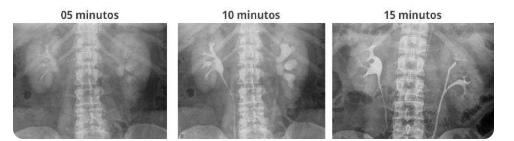

- Fase Pielográfica (Excretora - 5, 10, 15 min): Opacifica o sistema coletor (cálices, pelve, ureteres). Imagens com compressão abdominal podem ser usadas para melhor distensão dos cálices.

- Pielograma: Cálices côncavos e afilados. Ureteres finos com peristalse visível.